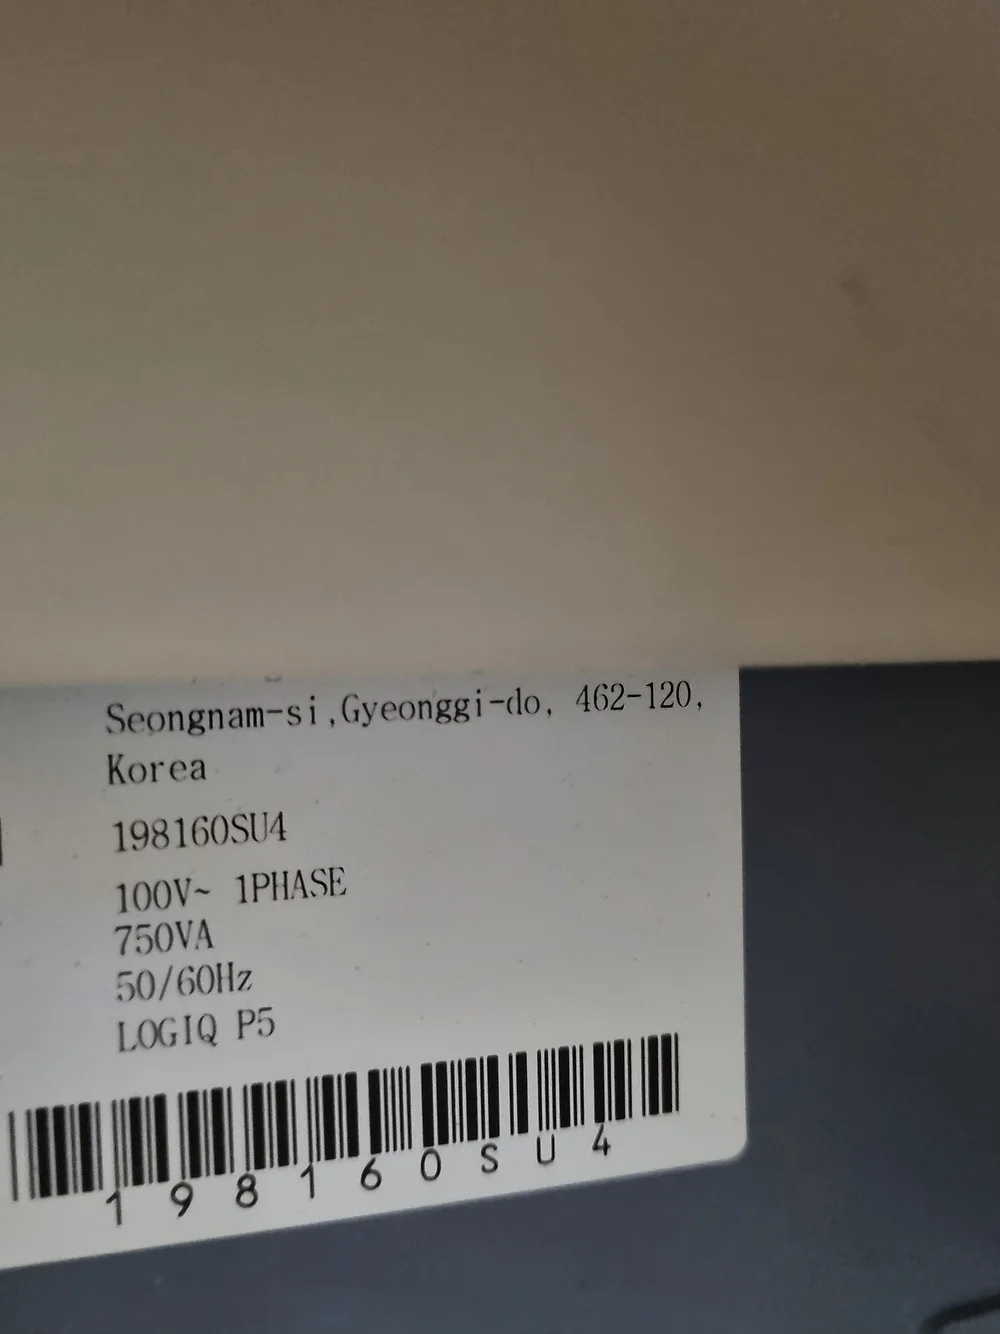

The LOGIQ P5 ultrasound system redefines compactness and efficiency while boasting a plethora of high-end features typically found in more expensive devices. Engineered for versatility and precision, this cutting-edge ultrasound scanner delivers unparalleled imaging quality across various medical specialties, including gynaecology/obstetrics, urology, cardiology, and paediatrics.

- Exceptional Performance: Despite its compact size, the LOGIQ P5 stands out as one of the most robust systems in its price range, offering features like CrossXBeam composite imaging, cardiac imaging, and speckle reduction for superior diagnostic accuracy.